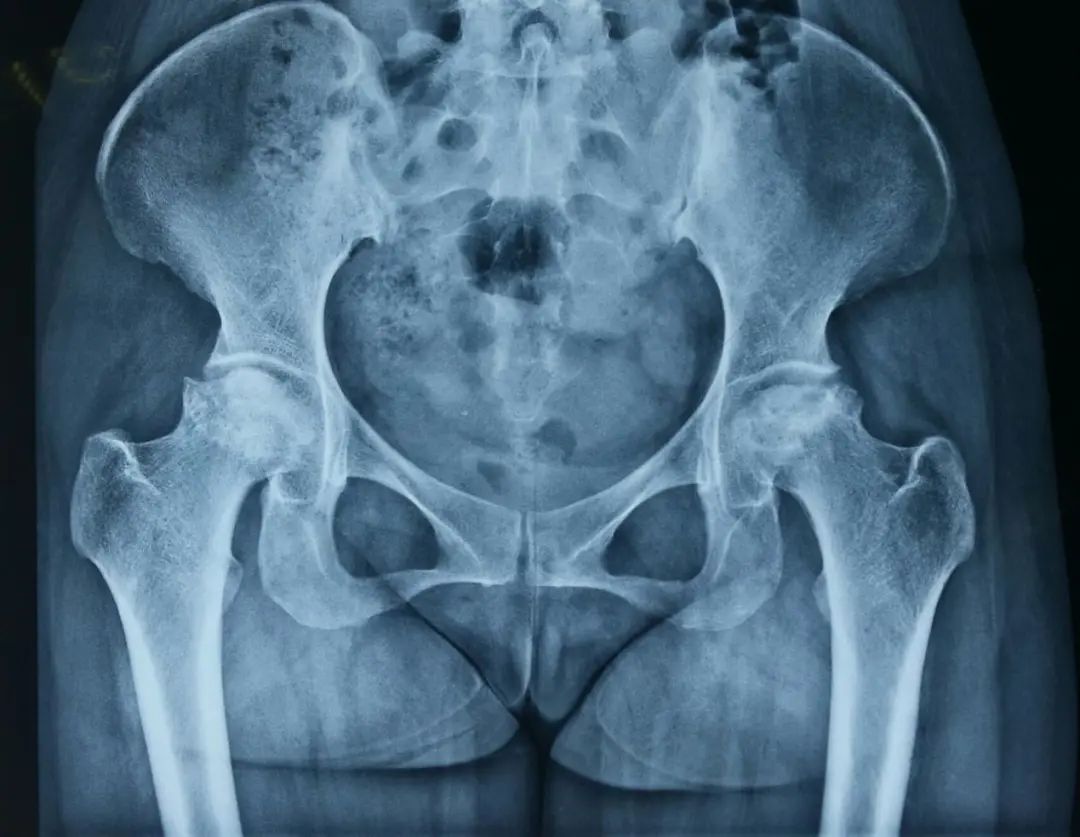

章先生,男,65岁,因双侧髋关节疼痛伴活动受限10余年入院,章先生此前因医疗信息获取困难、家住偏远山区就医困难等因素一直忍受髋关节疼痛,多次于当地基层医疗机构予以止痛药口服、草药外敷等保守治疗后无明显好转,决定来瑞安人民医院关节外科门诊就诊,刘敏主任予完善双髋X片检查,判断其双髋关节股骨头坏死程度较重,结合章先生严重的临床症状,考虑手术指征明确,建议章先生手术治疗。章先生经过考虑后,克服内心对手术的恐惧与顾虑,最终同意手术。

术前平片